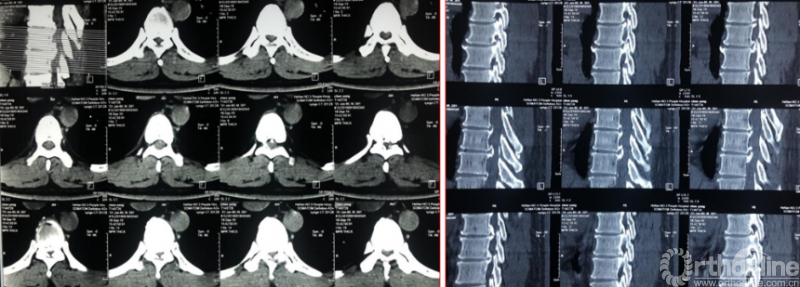

Case5:多节段胸椎后纵韧带钙化可视化治疗

影像学资料

术中资料

同一侧一次两个节段减压,择期对侧进行两个节段减压,两侧腹侧减压范围可达到硬膜囊360度环形减压效果。术后复查硬膜囊环形减压效果。关节突关节破坏较多,需长期佩戴支具固定,保证术后脊柱稳定性。

术后复查资料